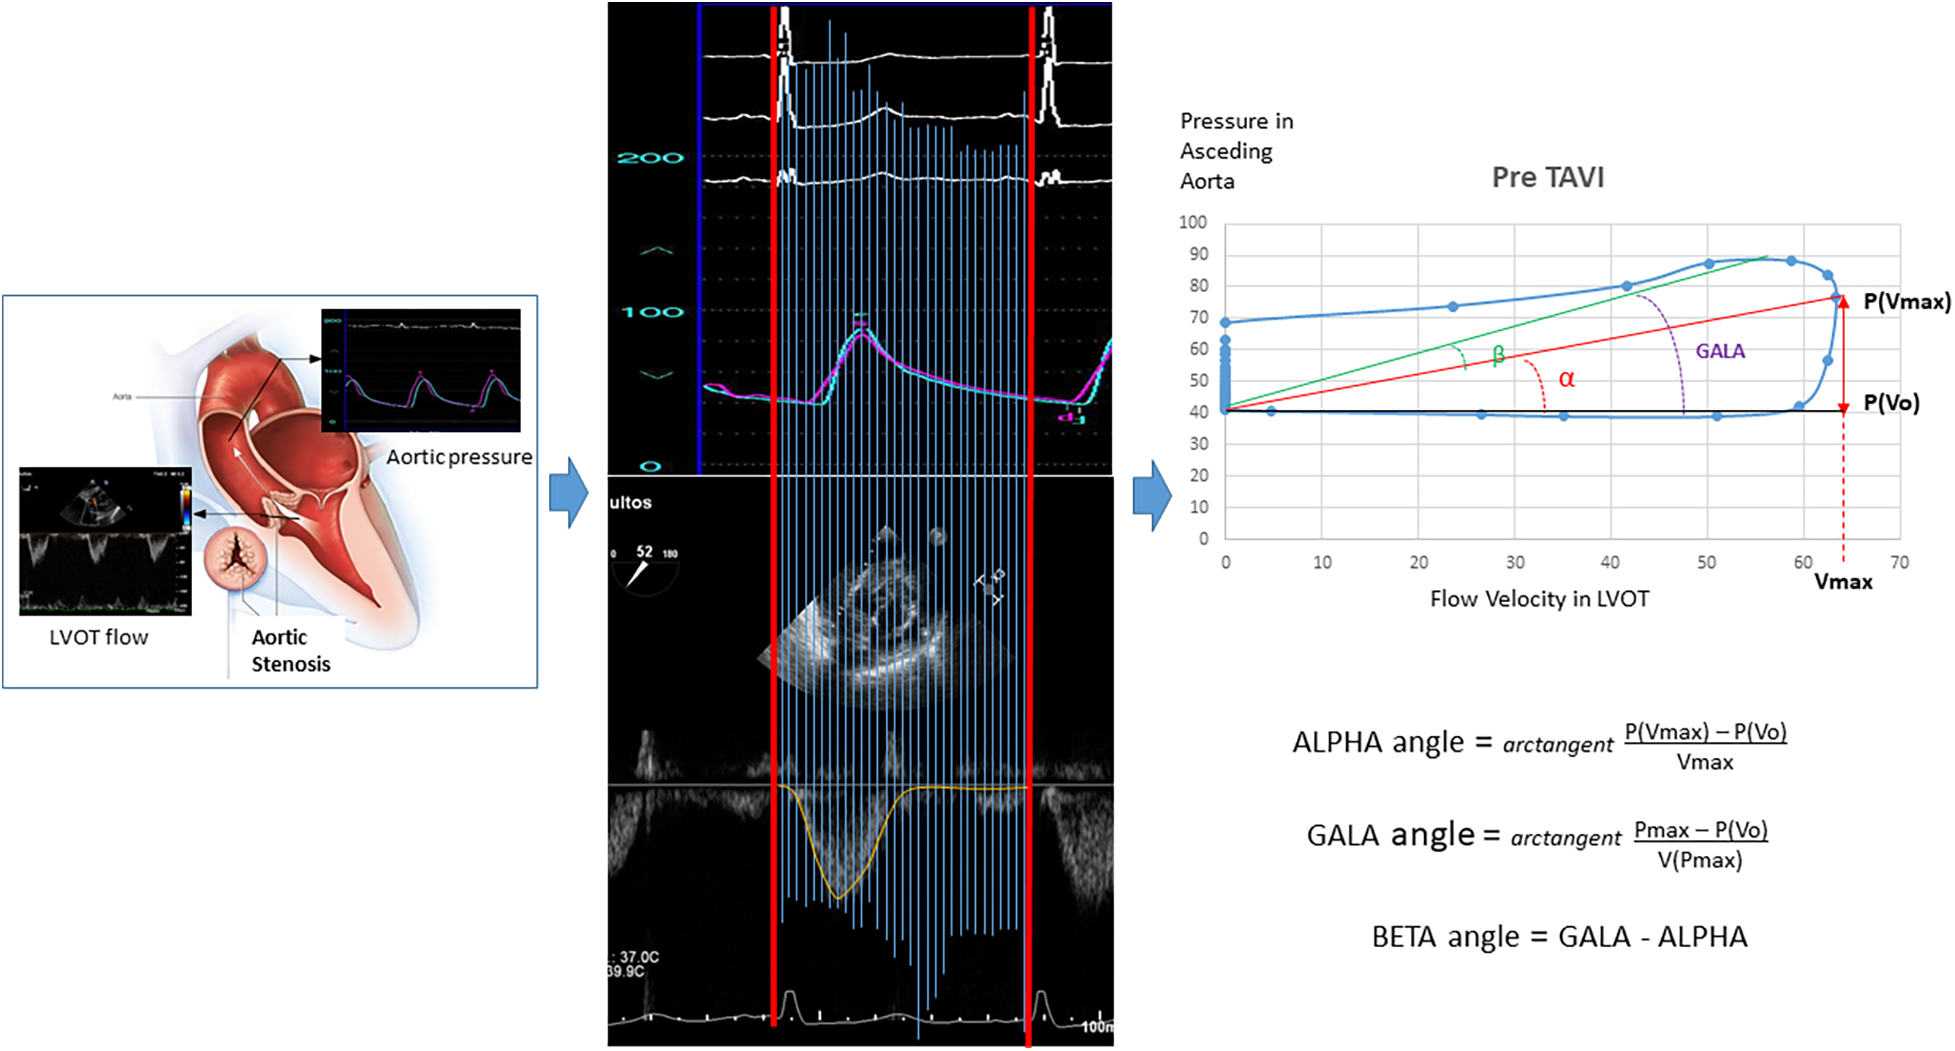

Construction and analysis of the flow velocity in LVOT–pressure in ascending aorta loops

The first step was to align both simultaneous VP records and create a mesh to obtain the same number of coincident points in time for velocity and pressure (Figure 1). The resulting images were processed using the WebPlotDigitizer application (13). The resulting data were saved in two independent vectors to later face them and create the loops with a program developed in R. From the loops, the angles and distances between the points defined by the maximum and minimum pressure–velocity values were calculated.

Figure 1

Construction and analysis of the loops for “flow velocity in left ventricular outflow tract/blood pressure in the aorta.” LVOT, left ventricular outflow tract.